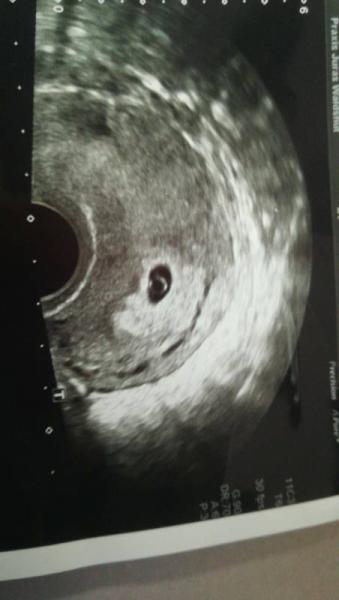

Also beim Arzt sah man dottersack und fruchthöhle... Viel deutlicher als beim letzten Mal. Leider kein Herzschlag

. Ultraschallbild im Anhang

Bild sieht für den Zeitraum genau richtig aus !

Ich finde, dass Bildchen passt und 6. Woche, da muss man noch keinen Herzschlag sehen. Kommt auch immer aufs Ultraschallgerät an!

Das sieht sehr gut aus!!! Bei mir sieht das Bild in der 6.Woche bei allen drei Kindern so aus! Herzschlag gab es bei allen 3 erst in der 7.Woche zu sehen.